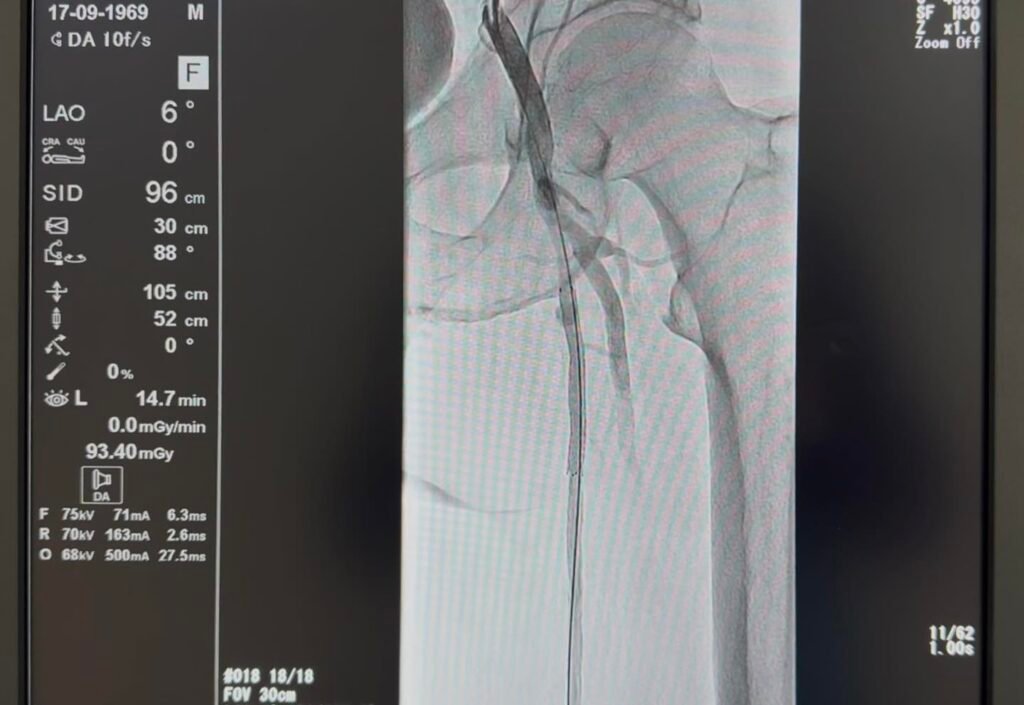

Percutaneous Transluminal Angioplasty (PTA) je minimalno invazivna endovaskularna procedura kojom se mehanički proširuje sužena ili okludirana arterija pomoću balon-katetera, a po potrebi se implantira i stent radi održavanja prohodnosti krvnog suda.

Ove intervencije predstavljaju značajan iskorak u zbrinjavanju pacijenata s oboljenjima krvnih sudova, posebno donjih ekstremiteta. Procedura, koja se u UKC Tuzla ranije izvodila intermitentno, izvedena je uz asistenciju kolega iz KBC Zagreb i sada će se kontinuirano primjenjivati u Klinici za invazivnu kardiologiju UKC Tuzla.